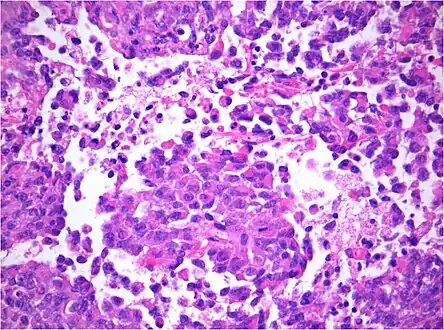

AT/RT and rhabdoid tumor share the term "rhabdoid" because under a microscope, both tumors resemble rhabdomyosarcoma.

-

AT/RT Histology with numerous rhabdoid tumor cells -

Rhabdoid Tumor Cell - 400X Magnification

Histology

The tumor histopathology is jumbled small and large cells. The tissue of this tumor contains many different types of cells including the rhabdoid cells, large spindled cells, epithelial and mesenchymal cells, and areas resembling primitive neuroectodermal tumor (PNET). As much as 70% of the tumor may be made up of PNET-like cells. Ultrastructure characteristic whorls of intermediate filaments are seen in the rhabdoid tumors (as with rhabdoid tumors in any area of the body). Ho and associates found sickle-shaped embracing cells, previously unreported, in all of 11 cases of AT/RT.[16]